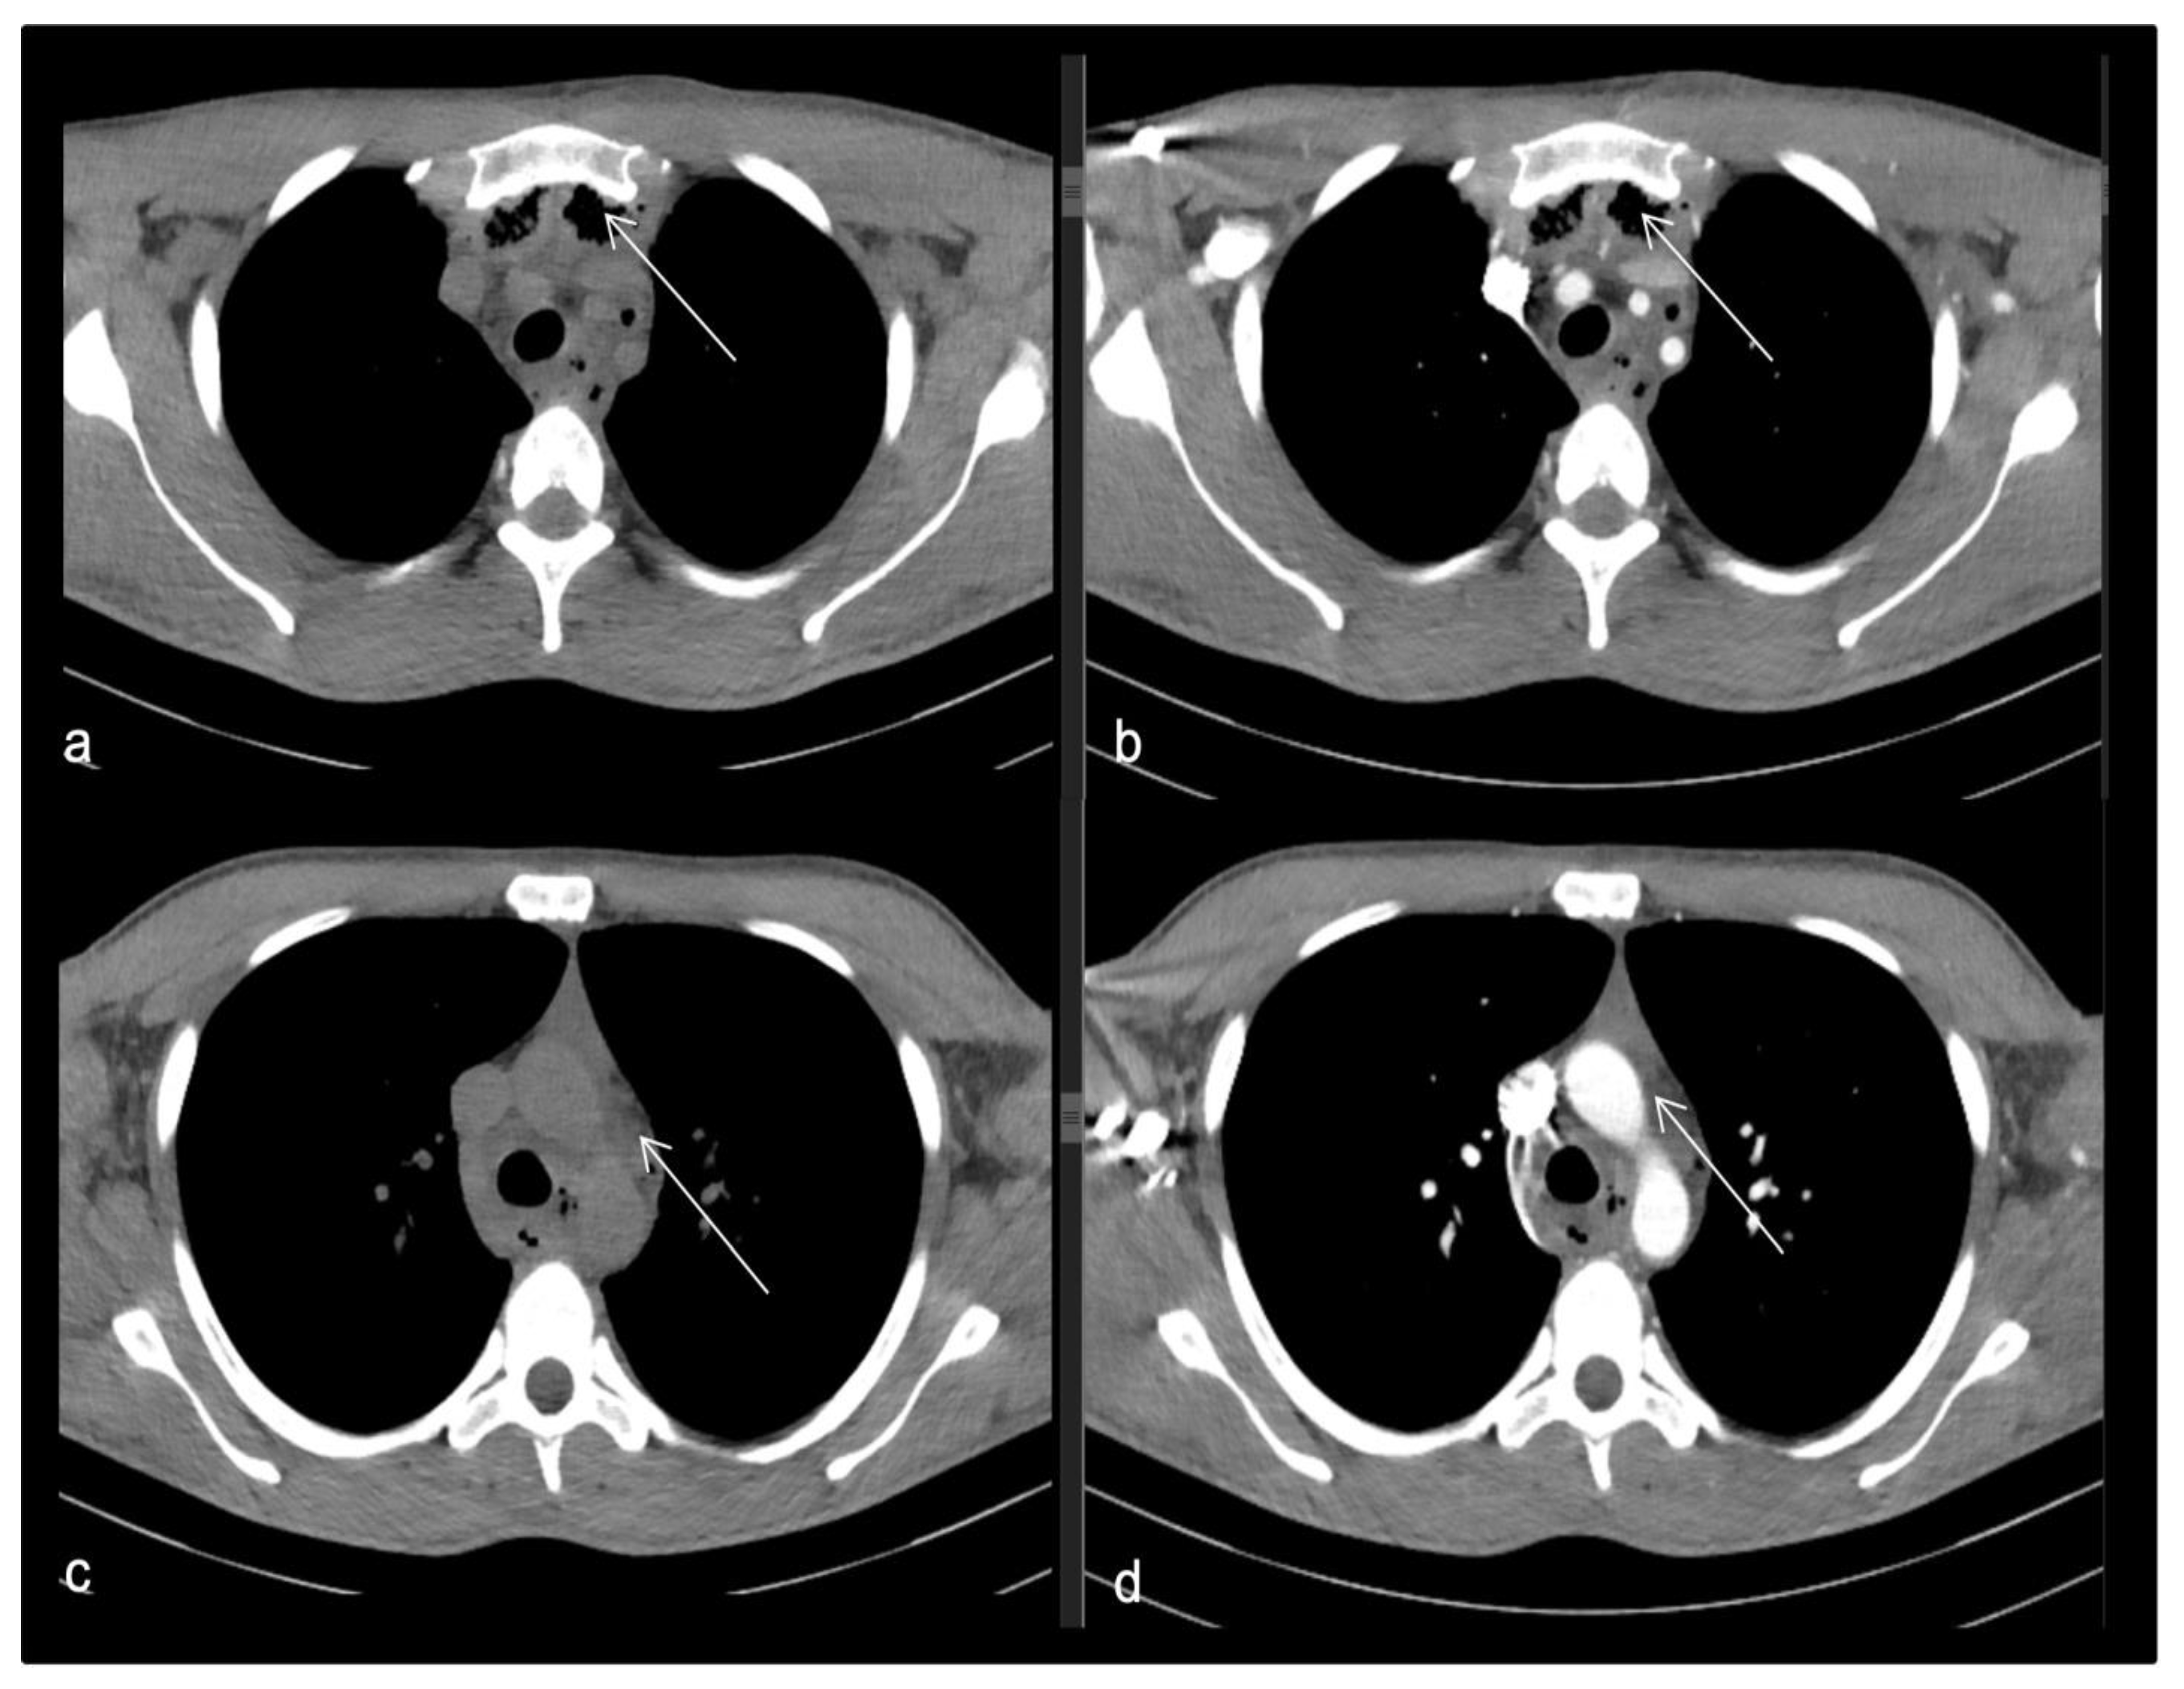

- Case 2.